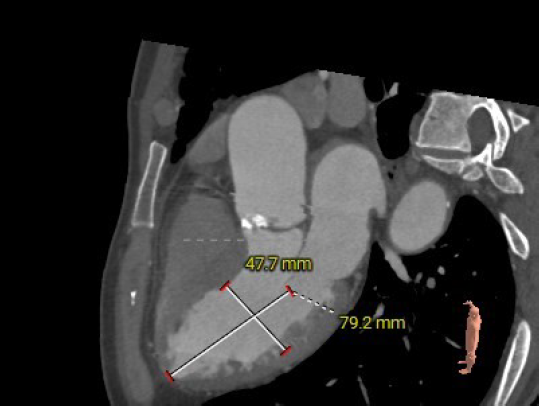

患者为71岁高龄男性,患者因反复胸闷15年,再发2月,5月慕名自行前来我院就诊。主动脉瓣听诊可闻及粗糙、高音调的喷射性收缩期杂音,余无特殊。术前超声显示瓣环直径28mm,左房37mm,左室收缩末内径55mm,左室流出道24mm。窦管高度17mm,内径39mm。瓣上最大流速3.7m/s,峰值压差56mmHg,平均压差34mmHg。诊断为主动脉瓣重度狭窄伴轻度关闭不全,二尖瓣轻中度反流。

主动脉根部评估:

左冠高度12.5mm右冠高度18.4mm,右冠脉开口高度大于瓣叶长度,SOV瓦式窦:平均周长径39.0mm,术中仍球囊预扩须密切注意冠脉灌注,STJ周长径39.2mm。

瓣叶重度钙化伴增厚,钙化分布不均匀,HU750积分1048mm²。

①患者为Type 0二叶式主动脉瓣,瓣叶重度钙化伴增厚,瓣环及左室流出道较大,瓣膜位移风险。术中选择25mm球囊预扩,减小瓣膜位移风险,并在预扩时密切注意根部限制性结构打开情况,及左侧冠脉灌注情况。

②患者瓣环、流出道、瓦氏窦、STJ等结构均较大,选择直径29mm瓣膜。